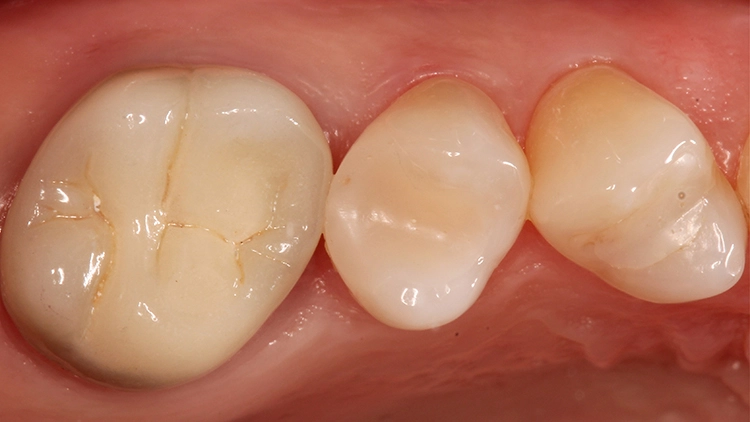

Die Abbildungen 18 und 19 zeigen dieselbe Situation nach 2 Jahren, die Abbildungen 20 und 21 nach 5 Jahren und die Abbildungen 22 und 23 nach 11 Jahren. Die direkte Kompositrestauration zeigte sich im gesamten Beobachtungszeitraum nahezu unverändert; es haben sich lediglich etwas Zahnsteinauflagerungen approximal gebildet, die im Rahmen der demnächst geplanten PZR beseitigt werden. Beim Nachkontrolltermin nach 11 Jahren wurde zudem eine erneute Röntgenaufnahme angefertigt (Abb. 24).

Gut erkennbar sind hingegen die perfekte Randdichtigkeit der Venus Diamond-Restauration an Zahn 25 und die sehr gute Röntgenopazität. Somit konnten dem inzwischen 11 Jahre alten Inlayersatz in direkter Technik mit Komposit durchweg gute Noten vergeben werden. Auch die Patientin zeigte sich mit der Versorgung nach wie vor sehr zufrieden – sie sah ihre damalige Entscheidung zu Gunsten der direkten Versorgungsvariante bestätigt.